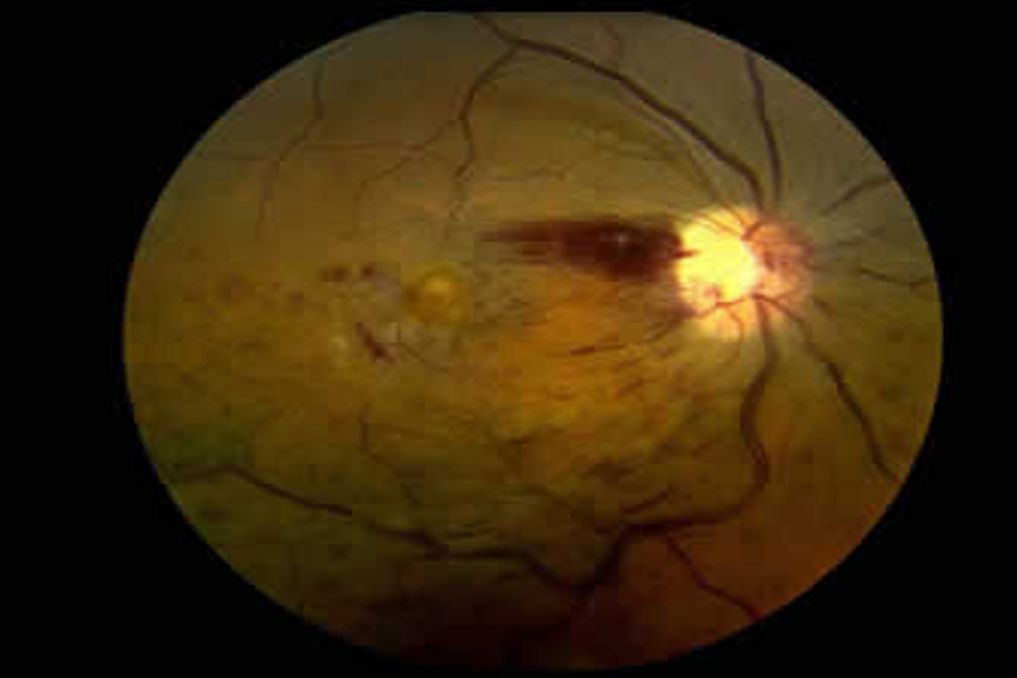

Retina Damar Tıkanıklıkları

Hastalıklar

Retinayı besleyen damarların tıkanması (RVO/RAO) ile ortaya çıkan ani, ağrısız görme kaybı; nedenleri ve tedavi seçenekleri.